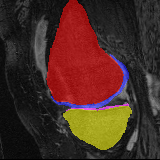

Knee MRI experiment: We test our method on 3D knee MRIs from the Osteoarthritis Initiative (OAI) 111https://nda.nih.gov/oai/ and corresponding segmentations of femur and tibia as well as femoral and tibial cartilage [1]. From a total of 507 labeled images, we use 200 for training, 53 for validation, and 254 for testing. To test registration performance we use 10,000 random image pairs from the test set. All images are affinely registered to an atlas built from the training images, resampled to isotropic spacing of 1mm, cropped to and intensity normalized to [0,1]. In addition, right knee images are flipped to be consistent with left knees. For training, the loss weights are , , and based on approximate hyper-parameter tuning. Note that when computing from the displacements, the image coordinates are scaled to [-1, 1] for each dimension following the convention in the interpolation function of PyTorch.

Results: All trained networks are evaluated using Dice overlap scores between predictions and the manual segmentations for the segmentation network, or between the warped moving segmentations and the target segmentations for the registration network. Tabs. 1 and 2 show results for the knee and brain MRI experiments respectively in Dice scores (%). Fig. 2 shows examples of knee MRI registrations and brain MRI segmentations.

Knee results: On knee MRIs, our method improves segmentation scores over separately learned networks by about 1.2 and 0.5, and registration scores increase by about 3.1 and 3.0, when training with 5 and 10 manual segmentation respectively. Especially for the challenging cartilage structures, our joint learning boosts segmentation by 1.4 and 0.7, and registration by 5.5 and 5.2 for N=5 and N=10 respectively.

Qualitative results: DA achieves more anatomically consistent registrations than the mono-networks on the knee (Fig. 2) and Brain MRI samples (see supplementary material).